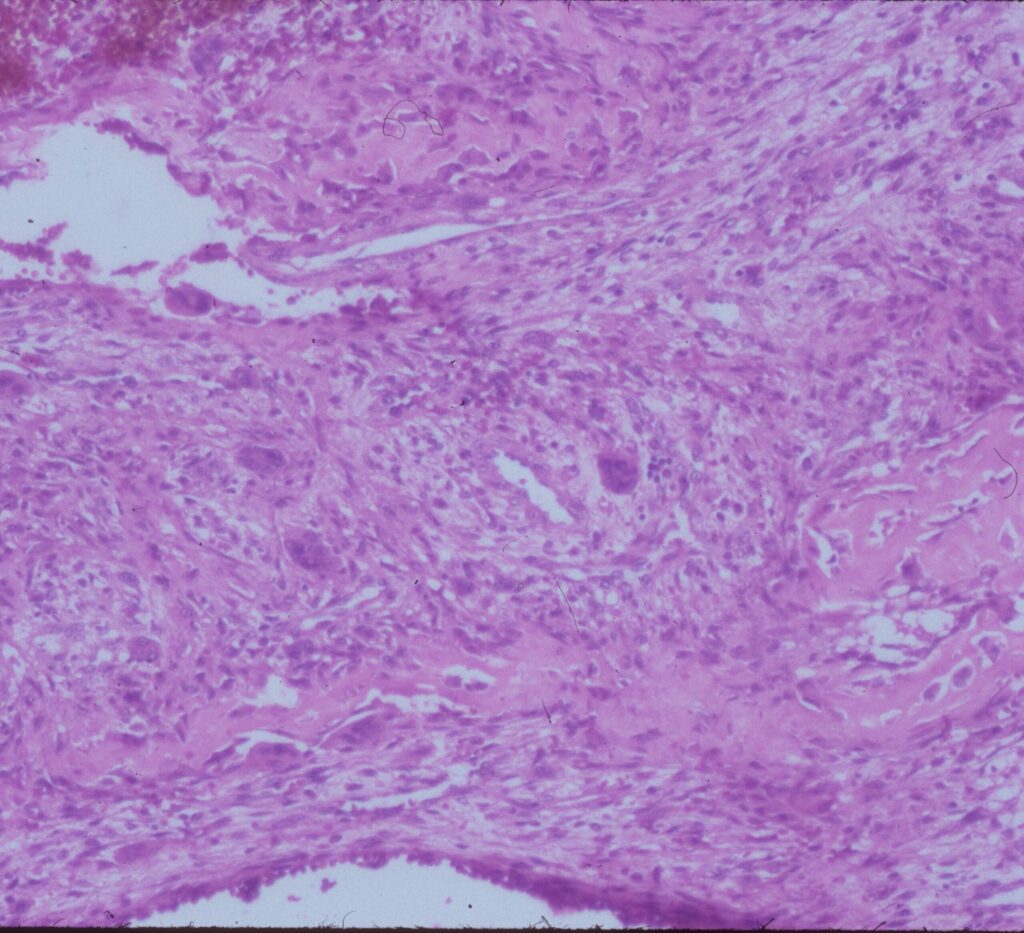

Microscopic Pathology

- Hemorrhagic tissue with large cavitary spaces divided by septum of spindle fibroblastic cells, inflammatory cells and few giant cells.

- Osteoid formation could be noted (reactive and benign in nature)

Fig 3b: Intermediate power of a septum of an ABC: There is no epithelial lining around the wall of the cavity filled with blood. There are spindle cells and scattered giant cells.